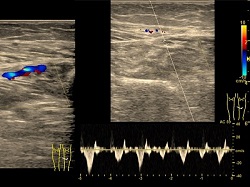

Doppler tętnic szyjnych

Badanie wykonywane jako przesiewowe do wykrywania małych zmian miażdżycowych i czynników ryzyka choroby wieńcowej. Wykonywane też z powodu zawrotów głowy w celu oceny przepływów w tętnicach kręgowych.

Zapis dopplerowski z tętnicy- małe zmiany miażdżycowe.

Doppler tętnic kończyn dolnych

Wykrywa zmiany miażdżycowe i zwężenia oraz niedrożności w tętnicach.

Zapis dopplerowski z tętnicy- duże zmiany miażdżycowe ze zwężeniami.